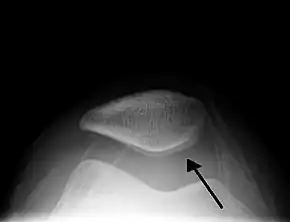

![]() Skyline view of the patella demonstrating a large joint effusion as marked by the arrow | |